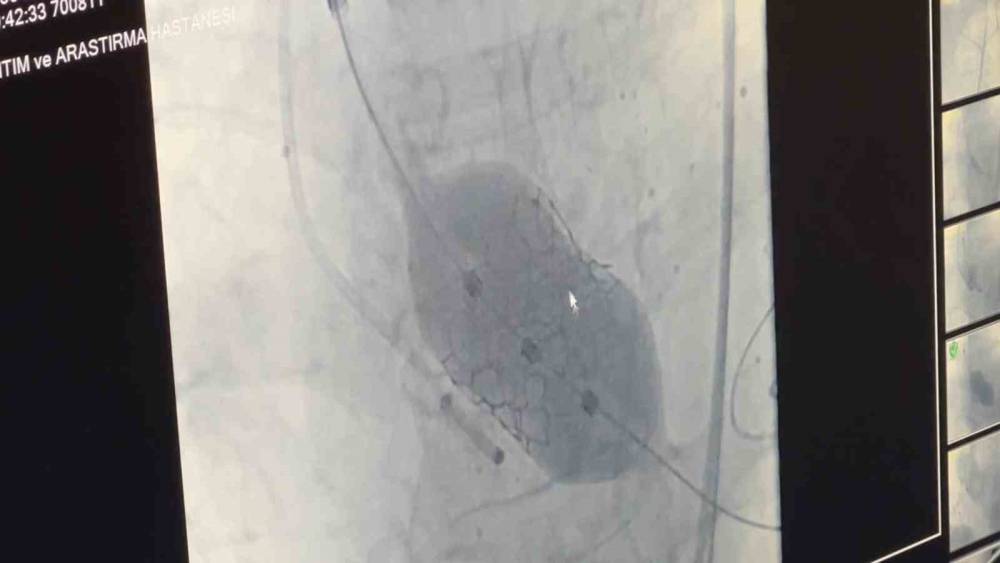

Samsun Eğitim ve Araştırma Hastanesi’nde 80 yaşındaki bir hastaya, nadir görülen dört yaprakçıklı aort kapağı nedeniyle transkateter aort kapak implantasyonu (TAVİ) yöntemiyle başarılı bir operasyon gerçekleştirildi. Operasyon, bu özelliği taşıyan vakalar arasında dünyada 18’inci, Türkiye’de ise ilk olma özelliği taşıyor. Amasya’nın Merzifon ilçesinde yaşayan Muzaffer Uslu (80), göğüs sıkışması ve baygınlık şikayetleriyle başvurduğu Merzifon Devlet Hastanesi’nden Samsun Eğitim ve Araştırma Hastanesi’ne sevk edildi. Tetkikler sonucu, normalde üç yaprakçıklı olması gereken aort kapağının dört yaprakçıklı olduğu belirlendi. Samsun Üniversitesi Tıp Fakültesi Kardiyoloji Ana Bilim Dalı Öğretim Üyesi Doç. Dr. Mustafa Yenerçağ, kapak değişiminin açık ameliyatla yüksek risk taşıması nedeniyle kapalı yöntem olan TAVİ işlemiyle çözüm sağladıklarını söyledi. "100 bin kişide 4 görülüyor" Doç. Dr. Yenerçağ, işlem öncesi yapılan tetkiklerde karşılaştıkları nadir bulgu hakkında ise "Hastanın TAVİ işleminden önce yapılan tetkiklerinde aort kapağının 3 yaprakçıklı olması beklenirken çok daha nadir görülen ‘Quadricuspid’ adı verilen 4 yaprakçıklı aort kapağı saptadık. Daha önce böyle bir vaka ile karşılaşmamıştık. Literatürleri, akademik çalışmaları inceledik. 4 yaprakçıklı aort kapağının toplumda 100 bin kişide 4 görüldüğünü, taradığımız uluslararası yayınlarda ise 4 yaprakçıklı aort kapağı bulunan sadece 17 hastaya TAVİ işlemi yapıldığını saptadık. Ülkemizden bildirilen vaka örneği bulamadık. Diğer ülkelerde yapılan vakaları detaylıca inceledik. İleri tomografik analizleri yaptık. Vakamıza detaylıca hazırlandık" dedi. 50 dakika içinde tamamlandı Operasyonu gerçekleştiren ekibi de paylaşan Yenerçağ, şunları söyledi: "Doç. Dr. Serkan Sivri, asistan doktorlarımız Berkan Öztürk ve Enes Kaya ile Anestezi Uzmanı Aynur Kaynar hocamızla beraber ekip halinde hastamıza başarılı TAVİ işlemini yaklaşık 50 dakika içerisinde tamamladık. Hastamızı 1 gün yoğun bakımda takip ettikten sonra servis takibine aldık. Nadir görülen bu 4 yaprakçıklı aort kapağına yaptığımız TAVİ işleminin prosedürel detaylarını literatüre kazandırmayı planlıyoruz. Bizden sonra bu nadir vaka ile karşılaşan meslektaşlarımıza yol göstermesi açısından referans olacaktır." Mustafa Uslu ise durumun iyi olduğunu söyledi.

Samsun Eğitim ve Araştırma Hastanesi’nde 80 yaşındaki bir hastaya, nadir görülen dört yaprakçıklı aort kapağı nedeniyle transkateter aort kapak implantasyonu (TAVİ) yöntemiyle başarılı bir operasyon gerçekleştirildi. Operasyon, bu özelliği taşıyan vakalar arasında dünyada 18’inci, Türkiye’de ise ilk olma özelliği taşıyor.

Amasya’nın Merzifon ilçesinde yaşayan Muzaffer Uslu (80), göğüs sıkışması ve baygınlık şikayetleriyle başvurduğu Merzifon Devlet Hastanesi’nden Samsun Eğitim ve Araştırma Hastanesi’ne sevk edildi. Tetkikler sonucu, normalde üç yaprakçıklı olması gereken aort kapağının dört yaprakçıklı olduğu belirlendi. Samsun Üniversitesi Tıp Fakültesi Kardiyoloji Ana Bilim Dalı Öğretim Üyesi Doç. Dr. Mustafa Yenerçağ, kapak değişiminin açık ameliyatla yüksek risk taşıması nedeniyle kapalı yöntem olan TAVİ işlemiyle çözüm sağladıklarını söyledi.

Doç. Dr. Yenerçağ, işlem öncesi yapılan tetkiklerde karşılaştıkları nadir bulgu hakkında ise "Hastanın TAVİ işleminden önce yapılan tetkiklerinde aort kapağının 3 yaprakçıklı olması beklenirken çok daha nadir görülen ‘Quadricuspid’ adı verilen 4 yaprakçıklı aort kapağı saptadık. Daha önce böyle bir vaka ile karşılaşmamıştık. Literatürleri, akademik çalışmaları inceledik. 4 yaprakçıklı aort kapağının toplumda 100 bin kişide 4 görüldüğünü, taradığımız uluslararası yayınlarda ise 4 yaprakçıklı aort kapağı bulunan sadece 17 hastaya TAVİ işlemi yapıldığını saptadık. Ülkemizden bildirilen vaka örneği bulamadık. Diğer ülkelerde yapılan vakaları detaylıca inceledik. İleri tomografik analizleri yaptık. Vakamıza detaylıca hazırlandık" dedi.

Operasyonu gerçekleştiren ekibi de paylaşan Yenerçağ, şunları söyledi:

"Doç. Dr. Serkan Sivri, asistan doktorlarımız Berkan Öztürk ve Enes Kaya ile Anestezi Uzmanı Aynur Kaynar hocamızla beraber ekip halinde hastamıza başarılı TAVİ işlemini yaklaşık 50 dakika içerisinde tamamladık. Hastamızı 1 gün yoğun bakımda takip ettikten sonra servis takibine aldık. Nadir görülen bu 4 yaprakçıklı aort kapağına yaptığımız TAVİ işleminin prosedürel detaylarını literatüre kazandırmayı planlıyoruz. Bizden sonra bu nadir vaka ile karşılaşan meslektaşlarımıza yol göstermesi açısından referans olacaktır."